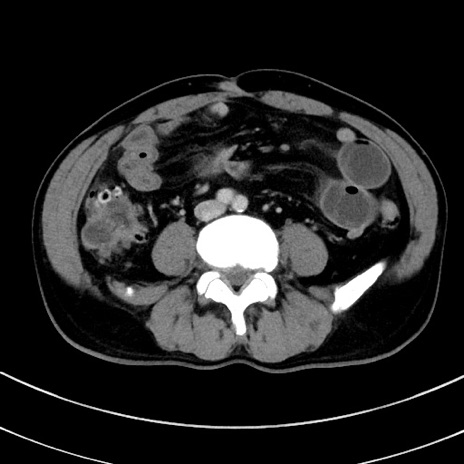

症例8(横断像)

【症例】 60歳代男性

【主訴】 黒色吐物

【現病歴】 4日前から嘔気自覚、2日前の朝食後にも嘔気あり、自分で手で嘔吐反射起こし嘔吐したところ血が混ざっていたため受診。

【既往歴】 5年前汎発性腹膜炎を伴う急性虫垂炎で手術、高血圧、前立腺肥大症、高脂血症

【身体所見】 腹部正中に手術癩痕あり 腹部平坦・軟圧痛なし膨満感あり

【データ】WBC 8400、CRP 4.54